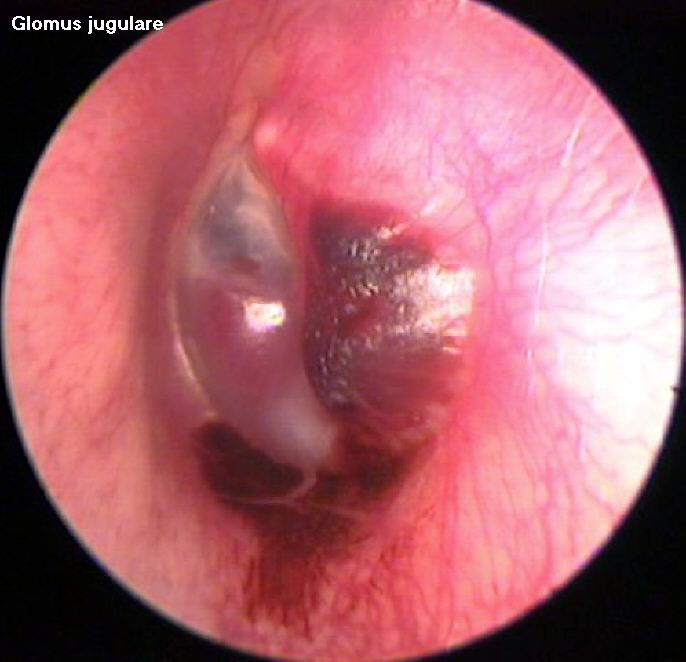

Presentation: These tumors are slow growing, with very little symptoms. The diagnosis may easily be missed. Infact the average delay between the onset of symptoms and diagnosis varied from 6 years to 15 years. The first symptoms generally follow middle ear involvement is easily overlooked. Pulsatile tinnitus and conductive deafness are the common presenting symptoms. A red mass behind an intact ear drum (rising sun sign) may also be seen. In some 30% of cases cranial nerve palsies are common. Facial nerve is affected most commonly.

Otoendoscopic picture of Glomus jugulare

Clinical features: Otoscopic examination reveals a characteristic, pulsatile, reddish-blue tumor behind the tympanic membrane that often is the beginning of more extensive findings (ie, the tip of the iceberg). When the drum is examined under a microscope will show a pulsation of the reddish mass behind the drum. On seigalisation the mass blanches. This sign is known as Brown's sign. This is pathognomonic of glomus tumor.